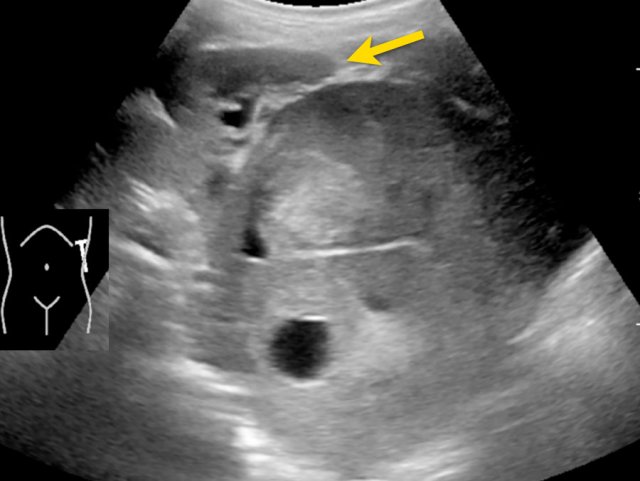

Ultrasound of a fifteen-month-old boy, who was first suspected of having a tumor in the left kidney.

Ultrasound shows a mass adjacent to the medial upper pole of the left kidney. It seems to be separate from the kidney. The mass is very inhomogeneous and has multiple calcifications.

These findings are more compatible with a neuroblastoma than a nephroblastoma.